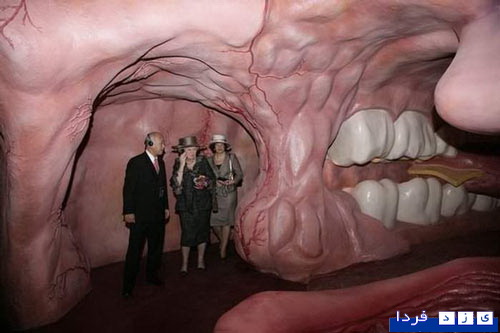

این ساختمان در هلند ساخته شده و با سفر به درون آن میتوان با بازدید از همه بخشها، از کارکرد درست یک بدن سالم آگاه شد و آموزش دید. ارتفاع این ساختمان که از نظر ظاهری پیکر انسانی نشسته است، 35 متر است.

این تصاویر عجیب و بی نظیری كه مشاهده می کنید مربوط به یك ساختمان واقع در كشور هلند است كه شبیه انسان ساخته شده و از تاریخ چهاردهم مارس 2008 برای بازدیدكنندگان فعال بوده است. بطوریکه با سفر به درون آن میتوان از تمامی قسمت ها و کارکرد درست یک بدن انسان سالم اطلاعات لازم را کسب کرد و در این تجربه جدید برای بازدیدكنندگان خصوصا دانشجویان رشته پزشکی این امکان فراهم شده بود تا با قسمتهای داخلی بدن انسان و نحوه فعالیتهای آنها از نزدیك آشنا شوند.

این بنای انسانی که از نظر ظاهری پیکر انسانی نشسته است، در كنار یك ساختمان شیشه ای با ارتفاع 35 متر بنا شده كه در جوار اتوبان A44 آمستردام به هاگو (Hague) قابل مشاهده است. گرچه این تصاویر شاید برای شما دوستان پرشین استار چندان جدید نباشد ولی آنچه مهم است اهمیت آموزش و ایجاد انگیزه برای سهولت در شناخت و درک بهتر ساختمان پیچیده و اسرار آمیز بدن انسان نسبت به نیاز محققین و دانش اندوزانی است که مایلند به گوشه ای از اسرار عظمت خلقت خداوند که همان اشرف مخلوقات است دست یابند.